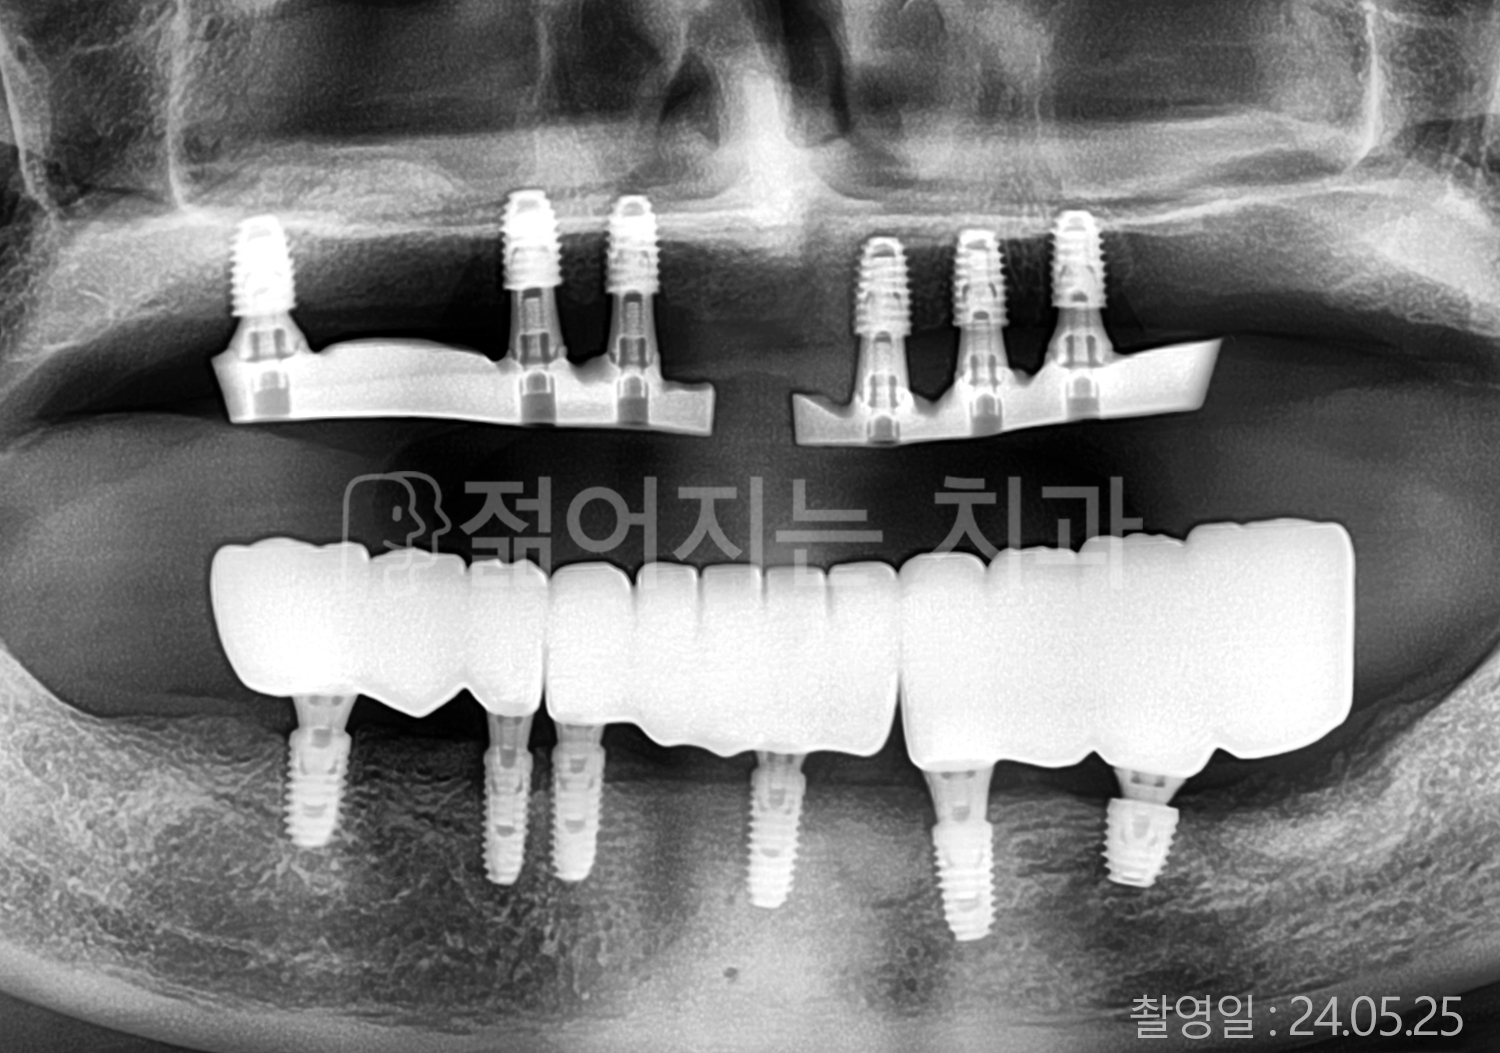

• 40대 전체치아 10개 이상 임플란트

• 70대 당뇨 전체치아 10개 이상 임플란트

• 60대 전체치아 10개 이상 임플란트

• 60대 고혈압, 당뇨, 고지혈증 전체치아 10개 이상 임플란트

• 50대 전체치아 10개 이상 임플란트

• 70대 고혈압, 당뇨 전체치아 10개 이상 임플란트

• 60대 고혈압 전체치아 10개 이상 임플란트

• 50대 고혈압, 당뇨, 고지혈증 전체치아 10개 이상 임플란트

• 60대 고혈압, 고지혈증 전체치아 10개 이상 임플란트